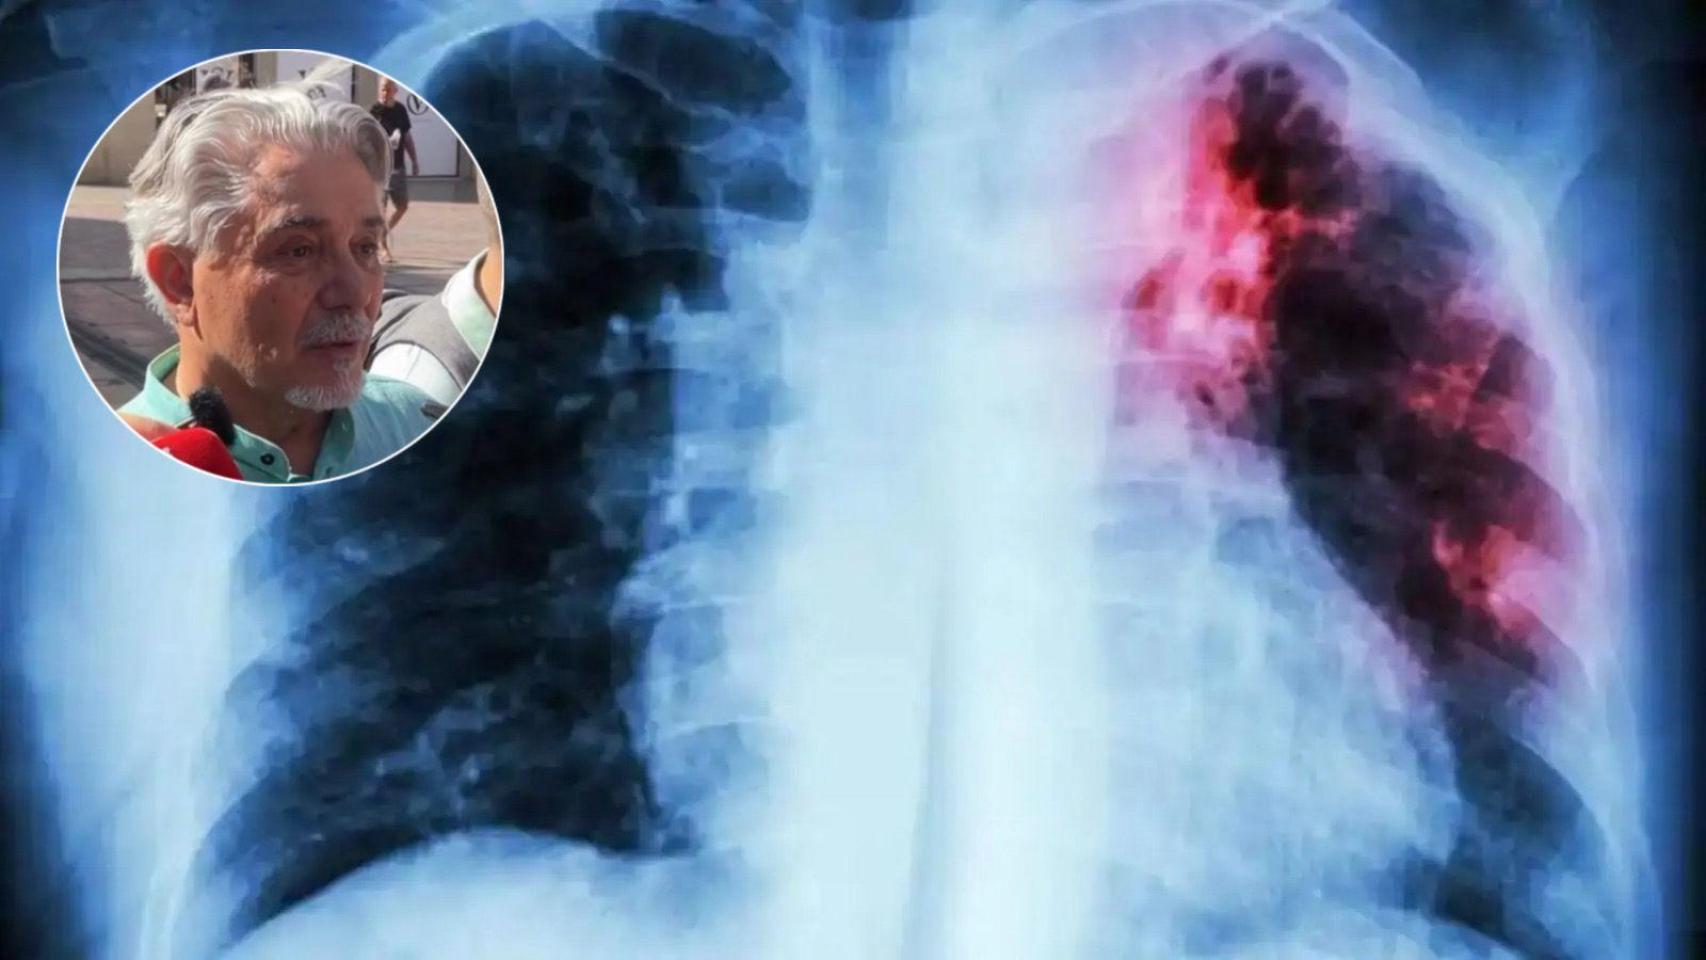

La investigación oncológica salva vidas y Rafael Santiago, paciente de cáncer de pulmón, lo ha vivido en primera persona. Tras varios años de lucha contra esta enfermedad, actualmente lleva una vida normal gracias a un ensayo clínico en el que participó desde el momento en el que le dieron el diagnóstico.

Rafael Santiago recibió que su diagnóstico era cáncer de pulmón en estadio 4 hace cuatro años. Desde entonces ha estado "entre la vida y la muerte", llegando al día de hoy porque al principio de su enfermedad decidió formar parte de un ensayo clínico para tener más posibilidades de superar la enfermedad.

“Recibí quimio, inmunoterapia, sufrí tres neumonías y hubo momentos en los que los médicos no sabían si lograría superarlo”, aseguró Santiago mientras celebraba el Día Mundial de la Investigación en Cáncer con la Asociación Española Contra el Cáncer en Málaga.

Pese a todo consiguió lograrlo y todo gracias al ensayo clínico al que se inscribió desde el principio de esa enfermedad. “Gracias a esa investigación puedo decir que llevo una vida normal y acudo a mis revisiones cada dos meses”, añadió.